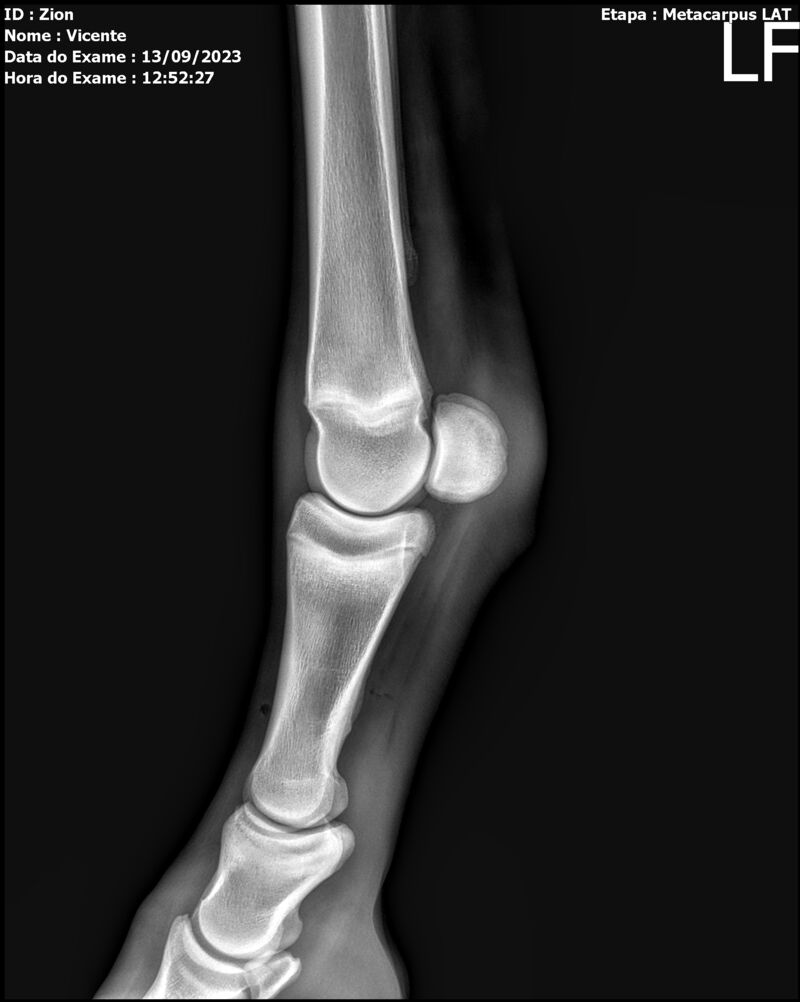

ZION ZC

Raça: BRASILEIRO DE HIPISMO

Sexo: MACHO - POTRO

Nascimento: 17/12/2022

Altura Aproximada: 1,51

Pel.: CASTANHO

Registro: EM AND

Vend.: VICENTE CONTE

Local : PORTO FELIZ/SP